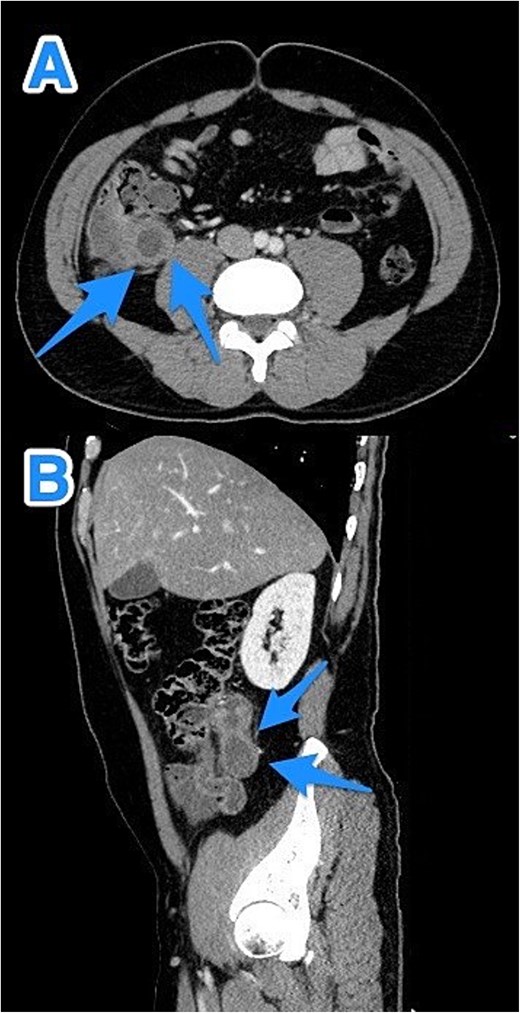

A 46-year-old male with a history of leukemia treated with chemotherapy and primary infertility presented with right lower quadrant abdominal pain of less than one day's duration. He reported associated nausea but no vomiting, changes in bowel habits, or fever. On systemic evaluation, the patient demonstrated stable vital signs, full consciousness, and alertness, with no evidence of severe pain. Abdominal examination revealed rebound tenderness in the RLQ, but the abdomen was otherwise soft, with no tenderness upon palpation of other regions. Laboratory investigations were within normal limits. Abdominal CT with contrast revealed evidence of appendiceal perforation. The liver showed moderate to severe steatosis, but no other remarkable abnormalities were detected (Fig. 5). Due to the perforation near the base of the appendix, a right hemicolectomy was performed. Histopathological examination of the appendix confirmed the diagnosis of LAMN (Fig. 6). The tumor extended to the visceral peritoneum through the perforation site, but there was no evidence of lymphatic, vascular, or perineural invasion. Four reactive lymph nodes were negative for tumor infiltration, and the pathologic TNM staging was pT4, pN0. The specimen also contained acellular mucin evacuated during the surgery. Postoperative recovery was uneventful, and the patient was later transferred to a higher center for comprehensive assessment and continued care.

CT abdomen and pelvis with contrast: (A) coronal, (B) axial, and (C) sagittal views reveal an appendix measuring 22 cm in the right iliac fossa, with edematous wall thickening, minimal surrounding fat stranding, and an adjacent fluid collection measuring 3.3 × 1.8 × 8.5 cm, consistent with a perforated appendix (arrows).